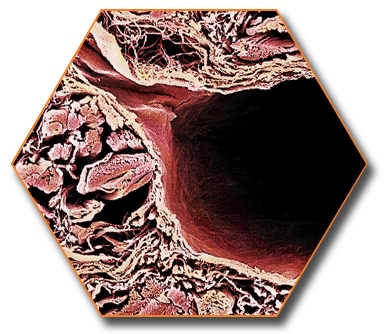

The BioHorizons conical, internally hexed connection features a number of unique design advantages focused on strength, durability and usability. The mating surfaces of the implant, abutment and abutment screw create a strong and durable precision fit as well as a predictable seal that isolates the inside of the implant from the oral biological environment. Using authentic BioHorizons parts will ensure a precision fit between the prosthetic component and implant, avoiding costly component failures that may occur from using third-party prosthetics.